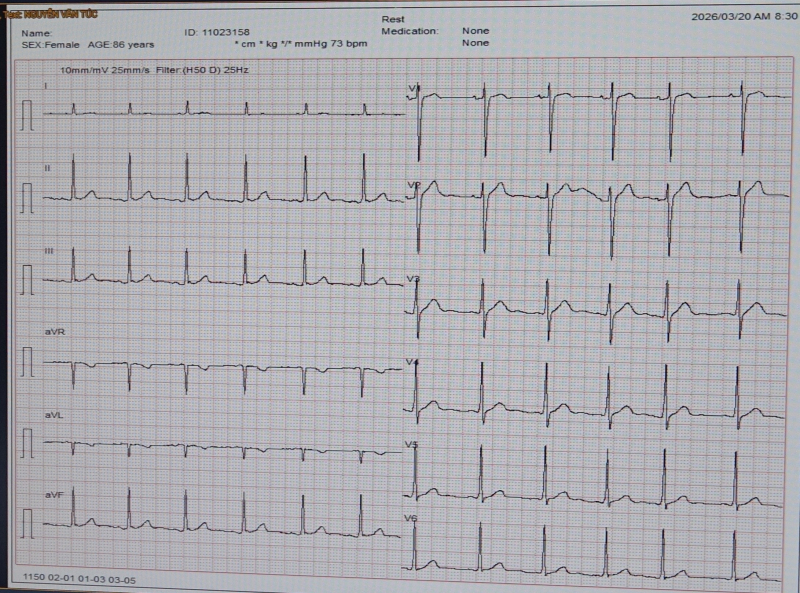

Đáng chú ý, trên hình ảnh MRI còn ghi nhận một số tổn thương nhồi máu nhỏ bên bán cấu não trái. Nghi ngờ bệnh nhân có thể có cơn rung nhĩ (do trên hình nahr điện tâm đồ làm nhiều lần không phát hiện rung nhĩ). Bệnh nhân nhanh chóng được đeo Holter điện tâm đồ 24h và kết quả có rung nhĩ cơn– một rối loạn nhịp tim nguy hiểm, có thể tạo cục máu đông trong tim và gây tắc mạch não. Rung nhĩ cơn đa phần ko phát hiện trên điện tâm đồ thường quy. Bệnh nhân đột quỵ được phát hiện rung nhĩ khi bác sĩ có kinh nghiệm đọc tổn thương trên MRI nghi ngờ và cho đeo holter điện tim 24h, 72h.

Hình ảnh: Điện tâm đồ

Ths.BS Giáp Hùng Mạnh, Trưởng khoa Thần kinh, VLTL – PHCN cho biết: việc phát hiện rung nhĩ ở bệnh nhân nhồi máu não có ý nghĩa đặc biệt quan trọng, bởi trên bệnh nhân này có thể cùng lúc tồn tại hai cơ chế gây đột quỵ: hẹp nặng động mạch cảnh và thuyên tắc mạch do rung nhĩ. Dùng thuốc điều trị nhồi máu não do rung nhĩ sẽ khác với điều trị nhồi máu não thông thường do các căn nguyên khác là phải dùng thuốc kháng đông thay vì dùng thuốc kháng kết tập tiểu cầu.